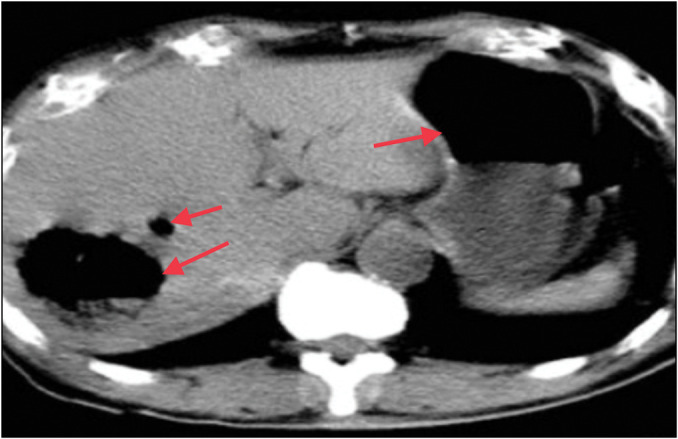

一名 53 岁的妇女因高烧伴寒战 15 天、右上腹疼痛 10 天前来外科急诊就诊。腹部 X 光片和胸部 X 光片显示右半膈下有游离气体。由于没有全身或局部腹膜炎的迹象,急诊开腹手术被推迟。随后,腹部造影剂增强计算机断层扫描显示该患者患有气肿性肝脓肿,在超声波引导下对脓腔进行了引流。

A 53-year-old woman presented to the surgical emergency with complaints of high-grade fever accompanied by chills for 15 days and pain in the right upper abdomen for 10 days. X-ray of the abdomen and chest X-ray revealed free gas under the right hemidiaphragm. As there were no signs of generalised or localised peritonitis, emergency laparotomy was postponed. Subsequently, a contrast-enhanced computerised tomography scan of the abdomen suggested an emphysematous liver abscess, which was managed by ultrasonography-guided drainage of the abscess cavity.